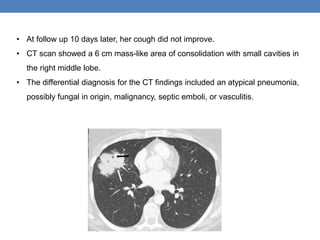

• At follow up 10 days later, her cough did not improve.

• CT scan showed a 6 cm mass-like area of consolidation with small cavities in

the right middle lobe.

• The differential diagnosis for the CT findings included an atypical pneumonia,

possibly fungal in origin, malignancy, septic emboli, or vasculitis.